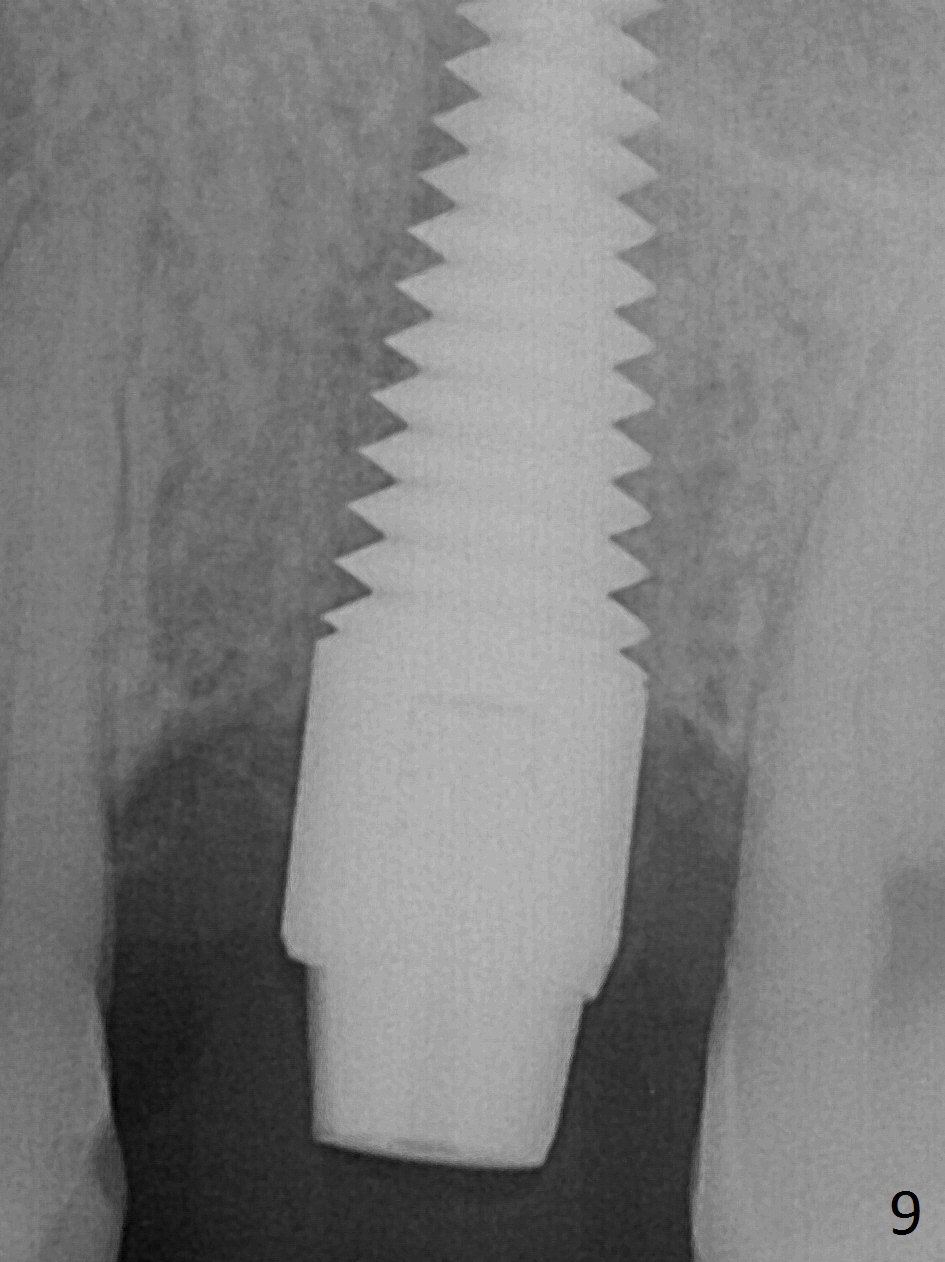

A much smaller implant should be used (e.g.4.5 mm) in order to save the septum. But the apical granulation tissue above the septum cannot be removed completely. There is no bone loss around the implant 4 months postop (Fig.9), although the gingiva is unhealthy because of lack of oral hygiene locally. The immediate provisional is not reseated with oral hygiene instruction. Impression will be taken in 2 weeks. Take photos to show disappearance of the fistula.